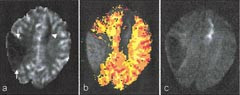

Når oksyhemoglobin deoksygeneres, går molekylets jernion (Fe2+) fra en diamagnetisk til en paramagnetisk tilstand. Paramagnetisk deoksyhemoglobin vil ved MR-opptak gi ujevnheter i magnetfeltstyrken i de nærmeste omgivelser. Såkalte T2*-vektede MR-opptak er følsomme for slike ujevnheter, på slike bilder vil områder med mye deoksyhemoglobin gi svakt signal og vil fremtre som mørke. Denne kontrasteffekten av blodets oksygeneringsgrad er blitt kalt BOLD (blood oxygen level dependent contrast). Effekten er særlig blitt utnyttet til å kartlegge ulike funksjonelle områder i hjernen.

Ved økt hjerneaktivitet (f.eks. pga. motorisk aktivitet, sensoriske stimuli eller tankevirksomhet) vil hjernecellenes oksygenforbruk øke. Dette gir en reflektorisk økt blodgjennomstrømning til det aktuelle området av hjernen. Den økte blodstrømmen overkompenserer for det økte oksygenforbruket, slik at veneblodet som drenerer de aktive områdene, inneholder mindre deoksyhemoglobin enn hva tilfellet er uten aktivitet. Mindre deoksyhemoglobin fører til økt MR-signal sammenliknet med hviletilstanden (13). Økningen i signal er for liten til å oppdages direkte visuelt, men ved å gjøre forsøk med avvekslende aktivitet og ingen aktivitet kan man ved hjelp av statistiske metoder oppdage og fargekode de områdene som veksler i signalintensitet i takt med forsøket. Metoden kalles gjerne på engelsk ”functional MRI” (fMRI), og er en teknikk som hovedsakelig har vært benyttet til forskningsformål. En svært nyttig praktisk anvendelse er utredning før hjernekirurgi for å kartlegge om viktige hjerneområder (f.eks. den motoriske bark) vil affiseres av inngrepet (fig 5) (14, 15).